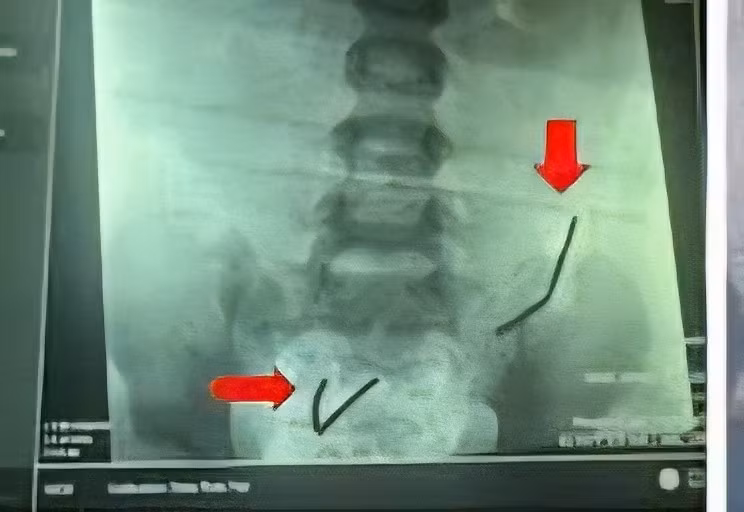

Chụp X-quang bụng ghi nhận dị vật nằm theo chuỗi ở ruột non đoạn trên và đoạn dưới, siêu âm ghi nhận tình trạng viêm ruột viêm phúc mạc.

Quá trình mổ, các bác sĩ phát hiện 2 chuỗi gồm 20 viên nam châm đã rỉ sét trong ruột bệnh nhi. Bệnh nhi bị thủng 8 lỗ ruột non, từ van hồi manh tràng lên trên 150cm, mỗi lỗ nhỏ đường kính 2-3mm.